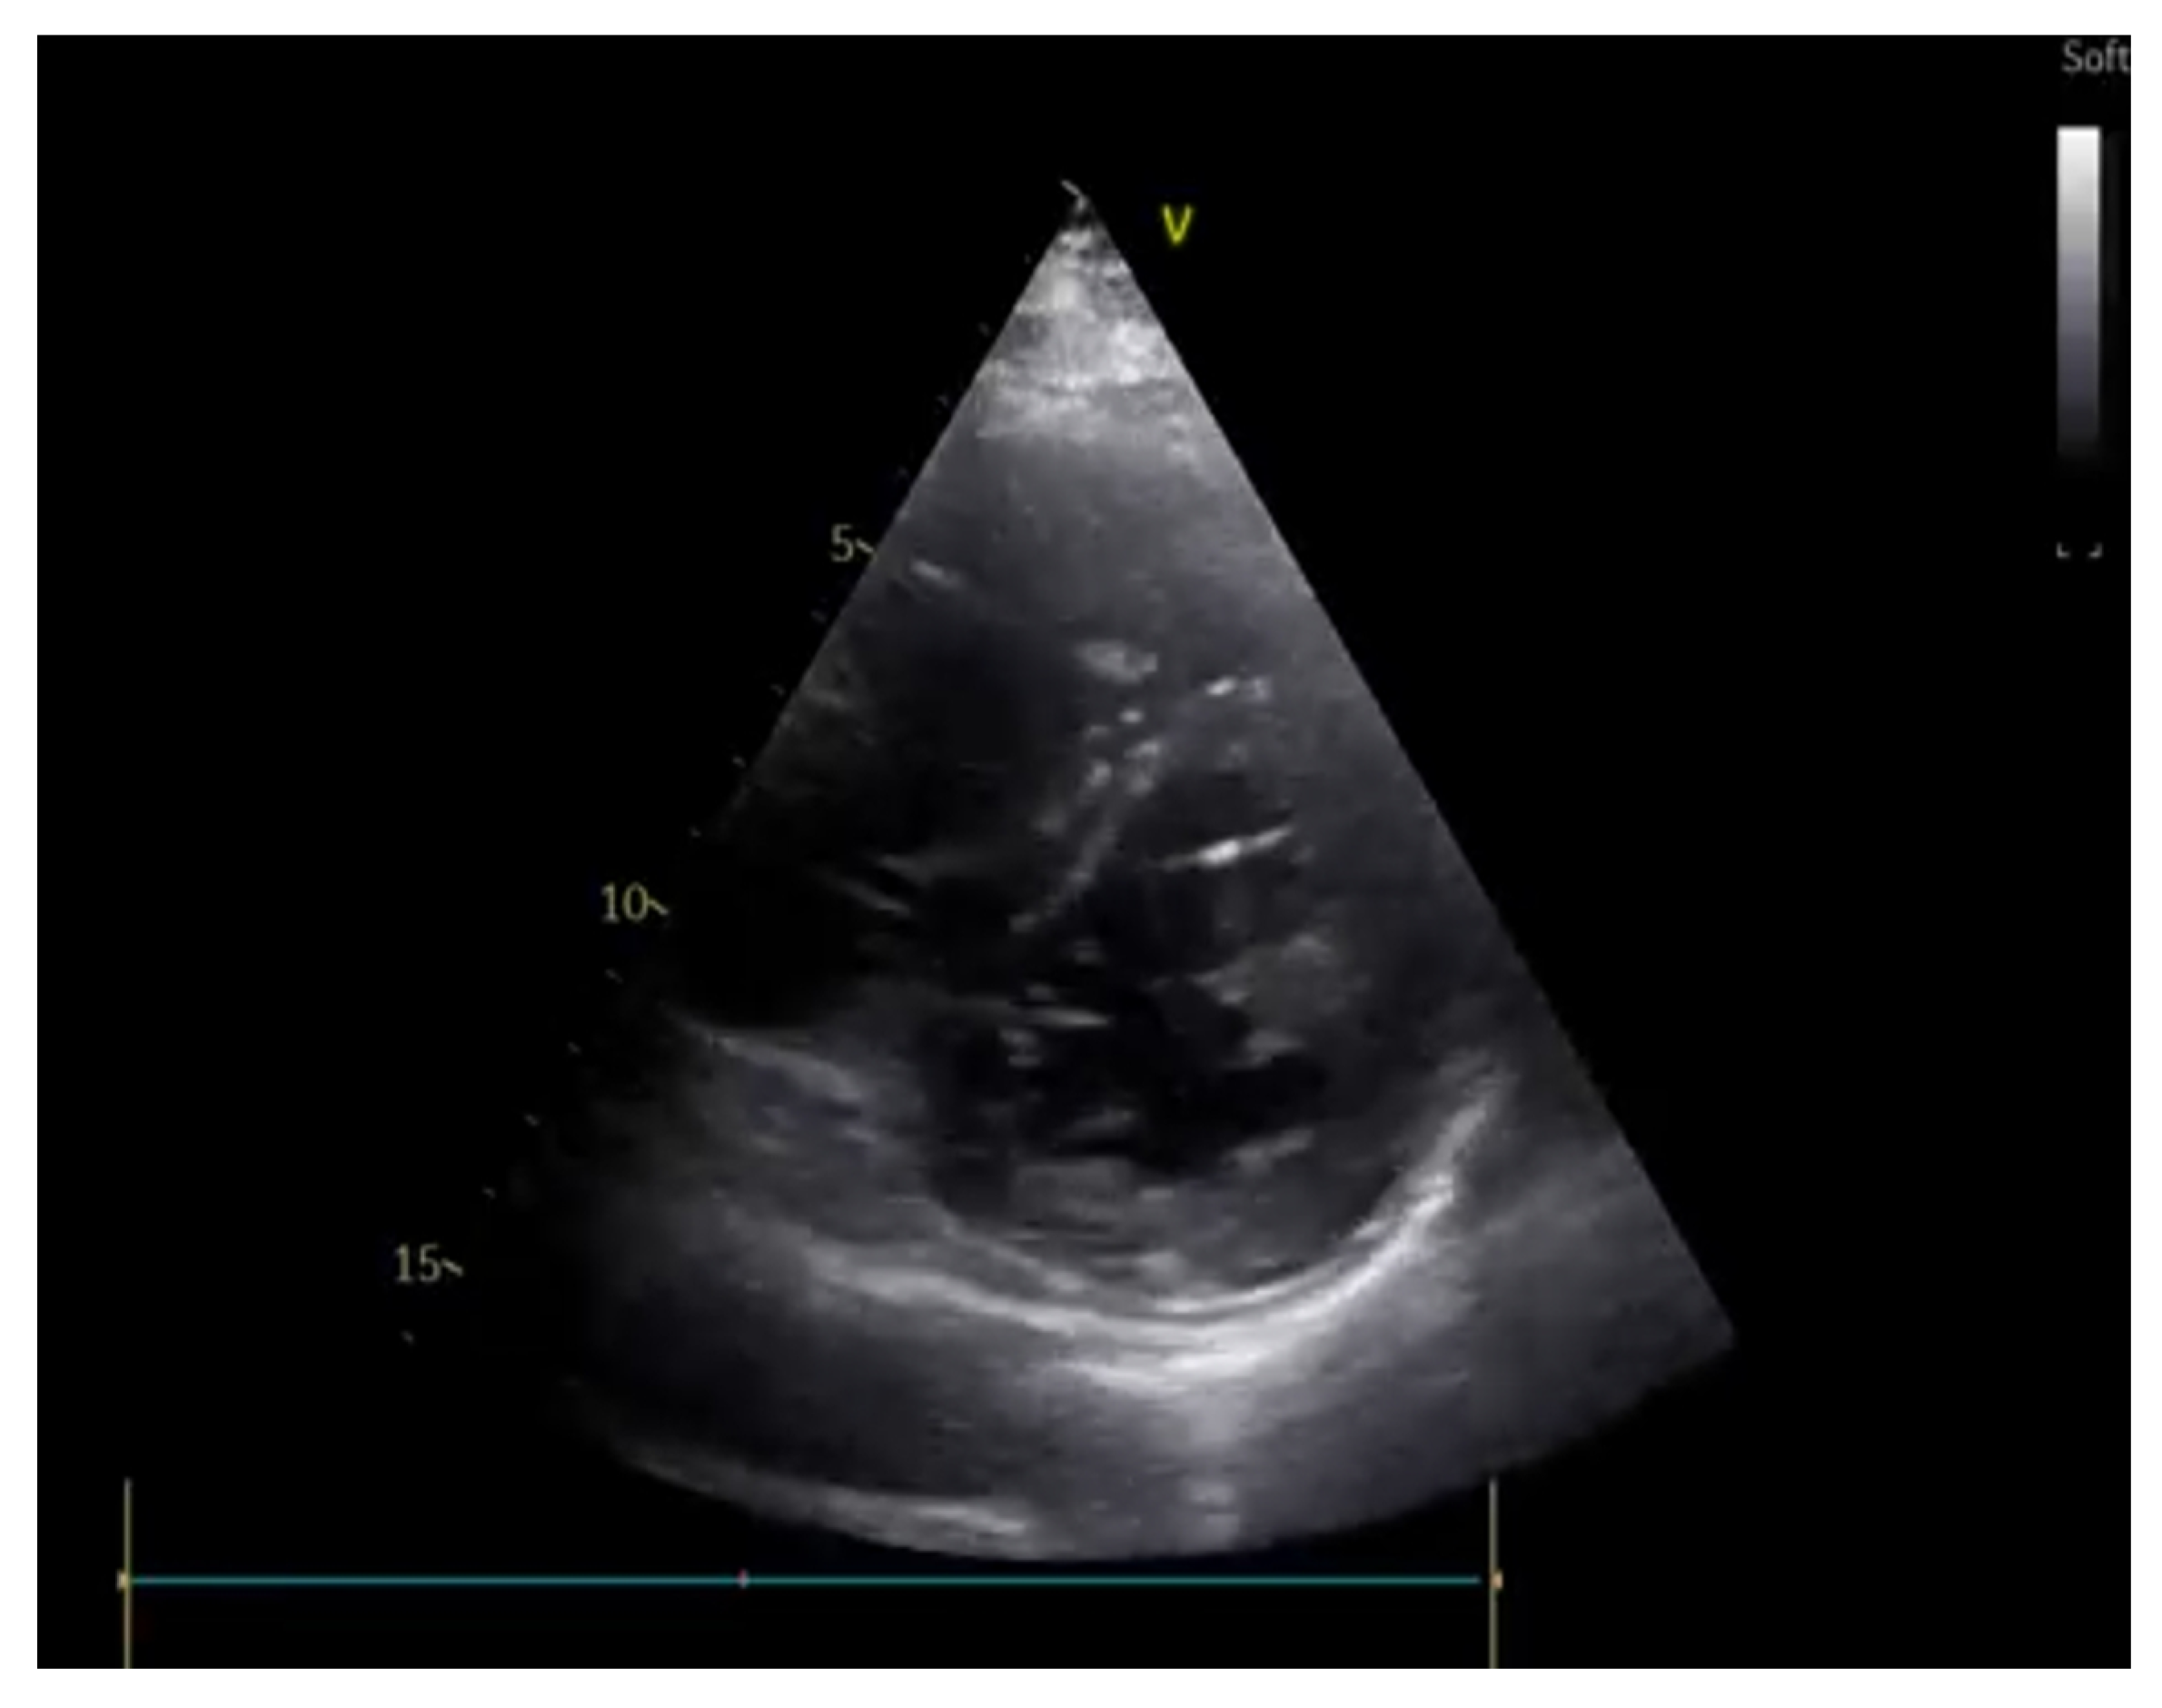

5. Deep-Vein Thrombosis

5.1. Protocol

5.2. Imaging

- Acute: the thrombus itself may not be visible. If detected, it is deformable with the force applied on the probe and with a regular surface; it is a distended vein.

- Subacute thrombus: (before six months and after clot formation) intermediate morphological changes that cannot be included in the chronic phase.

- Chronic post-thrombotic change: not compressible nor deformable with an irregular surface; the vein caliber may be normal or reduced.